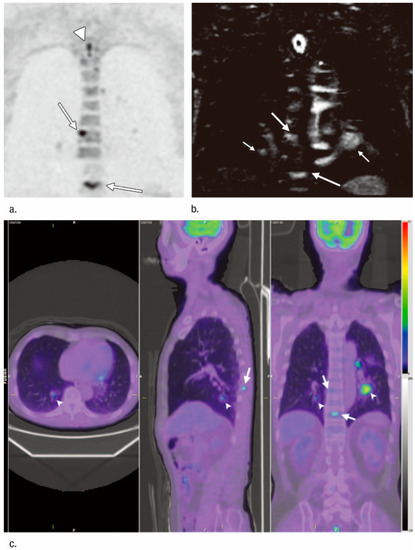

3.1. T-Factor Assessment

3.3. M-Factor Assessment